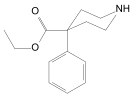

Prodines

- Allylprodine

- (α/β)-Meprodine

- Desmethylprodine (MPPP)

- PEPAP

- (α/β)-Prodine

- Prosidol

- Trimeperidine (promedol)

Structures